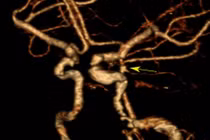

Qua trường hợp trên, các bác sĩ khuyến cáo người dân khi phát hiện tình trạng đau đầu, đặc biệt đau đầu cổ đột ngột, dữ dội thì nên thăm khám để phát hiện và điều trị kịp thời.

Vỡ túi phình mạch máu não gây xuất huyết dưới nhện còn có thể dẫn đến các hậu quả nặng nề như nhồi máu não, giãn não thất.... Người dân khi đau đầu, đặc biệt đau đầu cổ đột ngột, dữ dội cần cẩn thận.